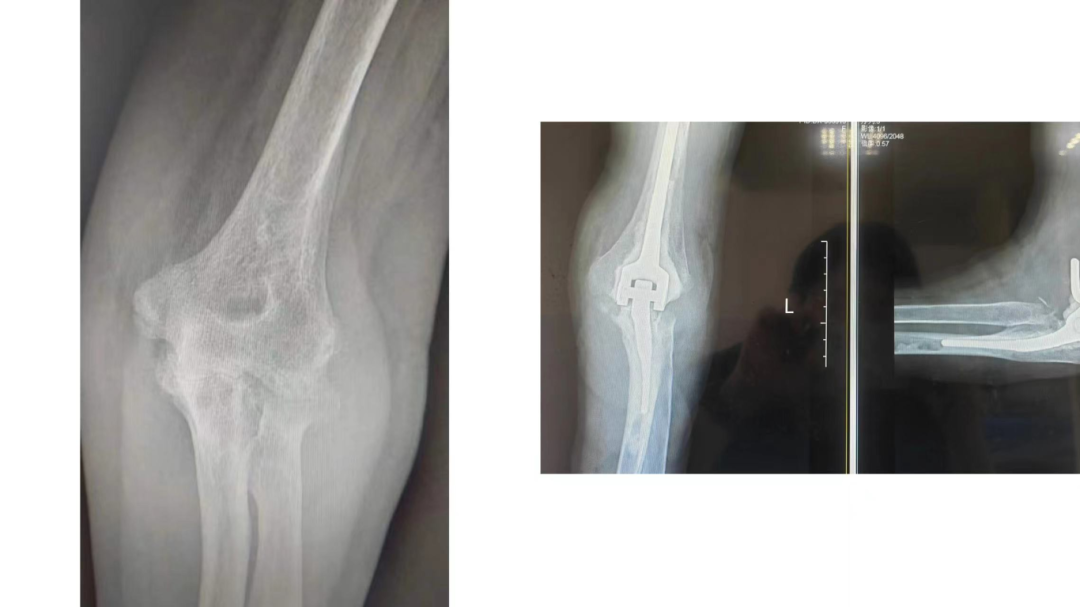

膝关节骨性关节炎高位截骨术

膝关节单髁置换术

肘关节炎类风湿性关节炎行肘关节置换术